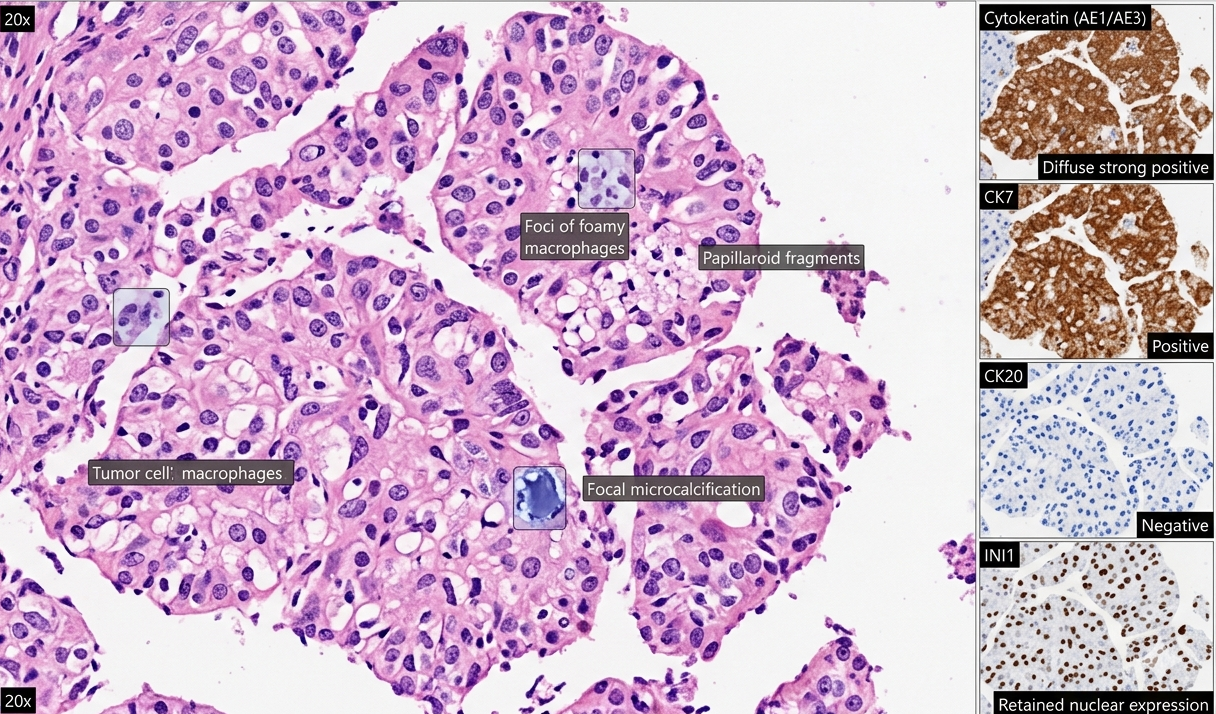

Histopathological and Immunophenotypic Reporting

Microscopy with hematoxylin & Eosin demonstrated sheets and papillaroid structures composed of tumor cells with hyperchromatic nuclei and abundant clear cytoplasm. No glandular or squamous differentiation was identified.

Immunohistochemistry confirmed epithelial origin with cytokeratin positivity and excluded multiple lineage specific markers. INI1 expression was retained, and beta catenin showed no nuclear localization.

Special staining did not demonstrate mucin.

Findings were consistent with poorly differentiated non-small cell carcinoma with clear cell features.

Fig 1: H&E and IHC from the left supraclavicular lymph node reveal metastatic epithelial malignancy composed of papillaroid fragments and solid sheets of monomorphic hyperchromatic cells with predominantly clear to focal eosinophilic cytoplasm, admixed with foamy macrophages and microcalcifications, without gland formation or keratinisation. Tumor cells show diffuse CK (AE1/AE3) and CK7 positivity, with negativity for CK20, p40, p63, and TTF1, excluding squamous and primary lung adenocarcinoma. Retained INI1, absent nuclear β-catenin, and PAS-D negativity further support the diagnosis. With ~70% tumor cellularity, features are consistent with metastatic non-small cell carcinoma.